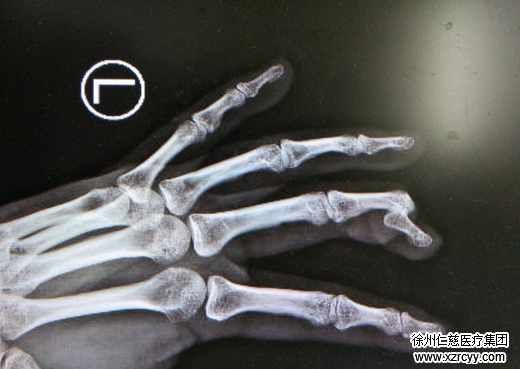

“患者来到医院时,左中指远节离断,创缘不齐,挫伤污染严重,伤口内见活动性出血及关节面外露,离断指体苍白、冷瘪。” 接诊的betway在线登陆手外科一病区主治医师潘勇介绍说,经过相关检查和准备,入院一个小时后,手外一病区的医护团队就为孙女士紧急实施了断指再植手术。经过三个小时的缜密手术,孙女士中指末端指节重新连接到了手指上。